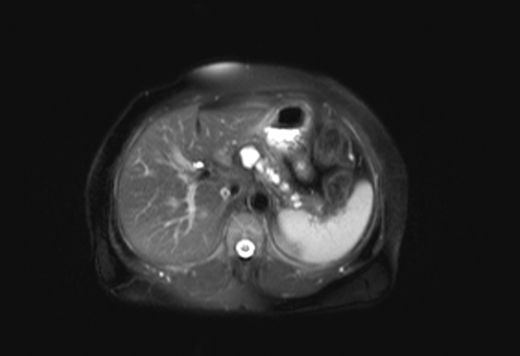

Bu belirtilerin varlığı, lezyonun boyutu, bulunduğu yer ve içeriği gibi faktörlere bağlı olarak değişiklik gösterebilir. Tanı Yöntemleri Komplike kistik lezyonların tanısı, çeşitli görüntüleme ve laboratuvar testleri ile konulmaktadır. Bu testler arasında:

Bu testler, lezyonun boyutu, şekli ve içeriği hakkında bilgi sağlayarak, hekimlerin doğru bir tanı koymalarına yardımcı olur. Tedavi Seçenekleri Komplike kistik lezyonların tedavi yöntemleri, lezyonun türüne, boyutuna ve bulunduğu organa bağlı olarak değişiklik göstermektedir. Tedavi seçenekleri arasında: